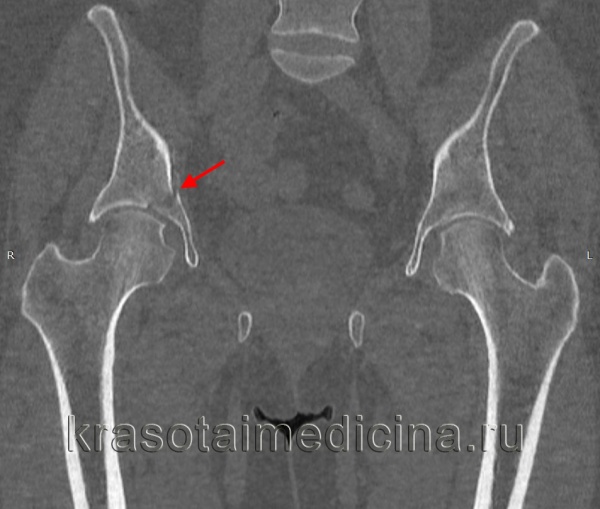

Для уточнения диагноза выполняют обзорную рентгенографию таза и рентгенографию поврежденного сустава в трех дополнительных проекциях. По возможности пациента направляют на КТ таза, поскольку эта методика позволяет более точно оценить тяжесть травмы и характер смещения отломков. Диагностическая ценность компьютерной томографии возрастает при повреждениях задней колонны и оскольчатых переломах.